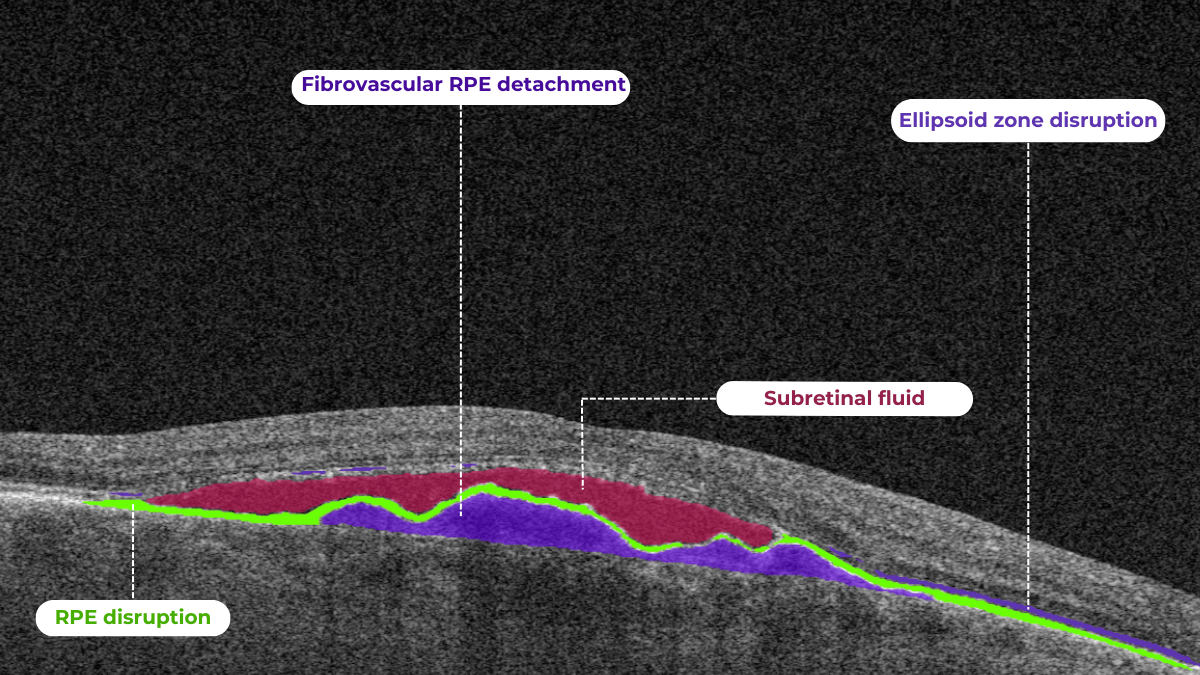

The platform visualizes what is going on with the retina using color coding. This means that every problem on the OCT scan will be colored differently and signed so you will be able to understand what is going on with your retina.

With the help of Altris AI, you will be able to see how the treatment affects you. For example, if you have fluid in the retina (that is not supposed to be there), you will be able to see if its volume is decreasing or increasing with the help of color coding.

Understanding complex eye conditions can be challenging for patients. Altris AI aims to bridge this gap by using color coding for pathologies and their signs, severity grading, and pathology progression over time within its OCT analysis.

With Altris AI, scans are color-coded for instant interpretation: all the detected pathologies are painted in different colors, highlighting the littlest bits that the unprepared eye of a patient would miss otherwise.

This easy-to-understand visual system empowers patients. They can clearly see what’s happening within their eyes and track the progress of any conditions during treatment.